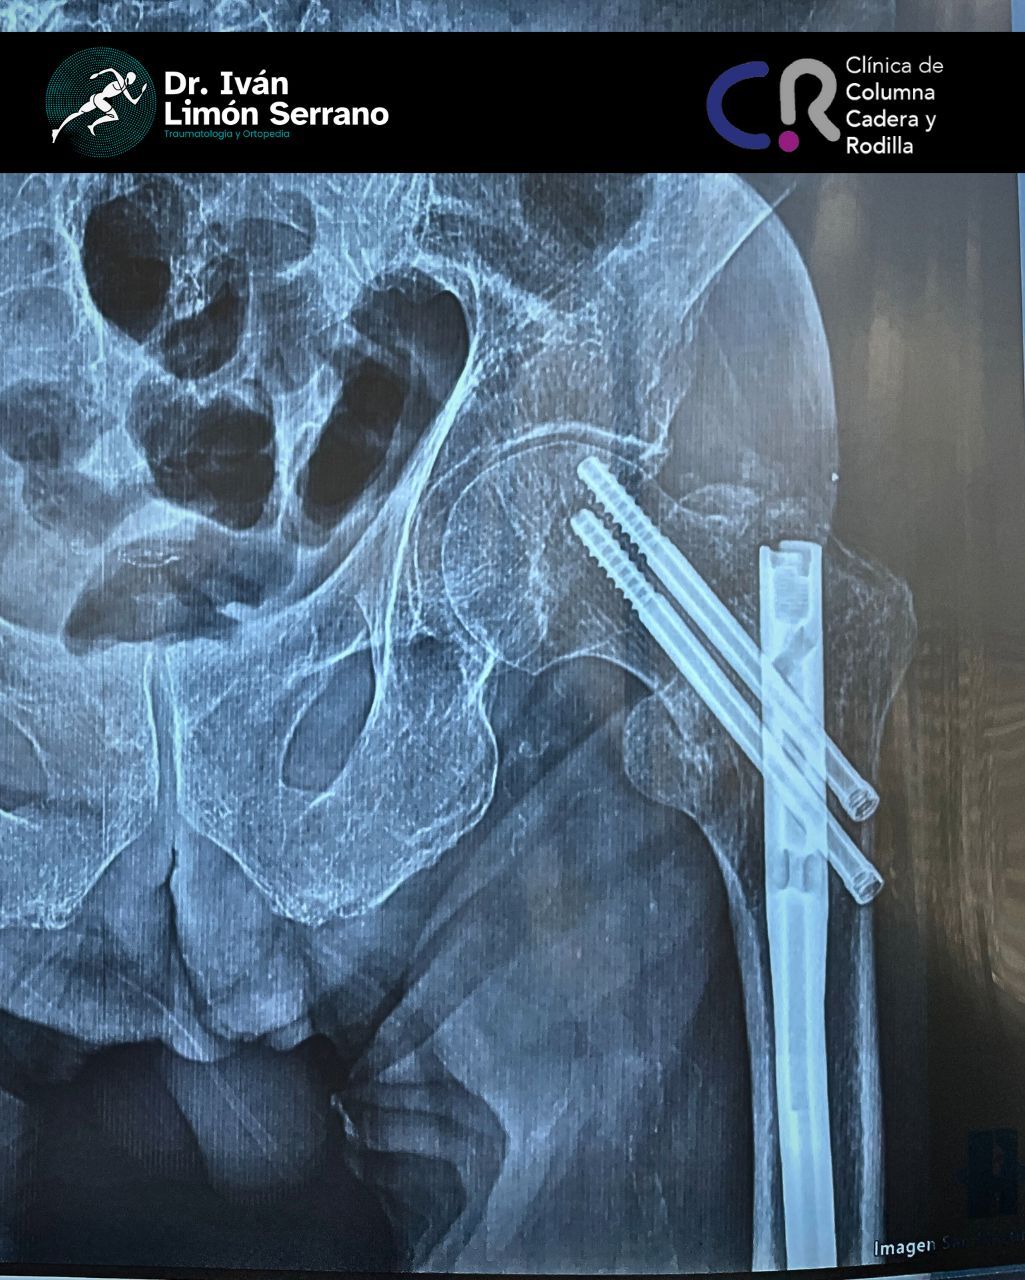

• Prótesis de rodilla